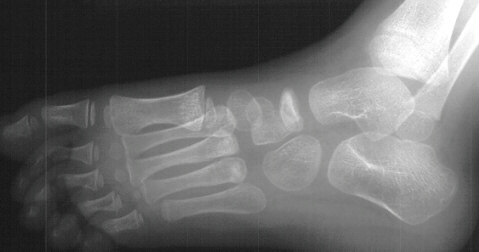

Radiographs of the patient were obtained on her presentation to our clinic. These confirmed the finding of increased radiodensity of the navicular with a flattened appearance to the ossific nucleus. Furthermore they revealed increased density and callus formation in the proximal 1st through 4th metatarsals. This was consistent with multiple non-displaced fractures of the proximal metatarsals secondary to trauma. While Kohler's disease cannot be ruled out in this case, it is more likely that the patient had symptoms produced by her metatarsal fractures. The radiographic appearance of the tarsal navicular almost certainly preceded the acute traumatic event. Therefore, she probably had metatarsal fractures superimposed on irregular ossification of the tarsal navicular giving a clinical picture similar to Kohler's disease.